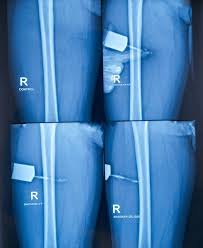

사이노그램은 체내 영상을 촬영하는 기술의 한 방식으로, 여러 각도에서 X선을 촬영한 뒤 이를 컴퓨터로 복원하여 3차원 영상을 만드는 기술입니다. 이 기술은 지구과학과 미적분이 연계된 연구에도 활용됩니다.

이 화석의 구조를 정확하게 관찰하기 위해 여러 각도에서 X선 촬영을 하고, 사이노그램 기술을 이용하여 3차원 영상을 복원하였습니다. 사이노그램 자료에서는 X선 흡수량을 2차원 평면상에 표현한 뒤, 이를 라돈변환의 역과정인 역라돈변환을 통해 3차원 영상을 구합니다.

이를 통해 화석 내 생물의 정확한 3차원 구조를 확인할 수 있습니다.